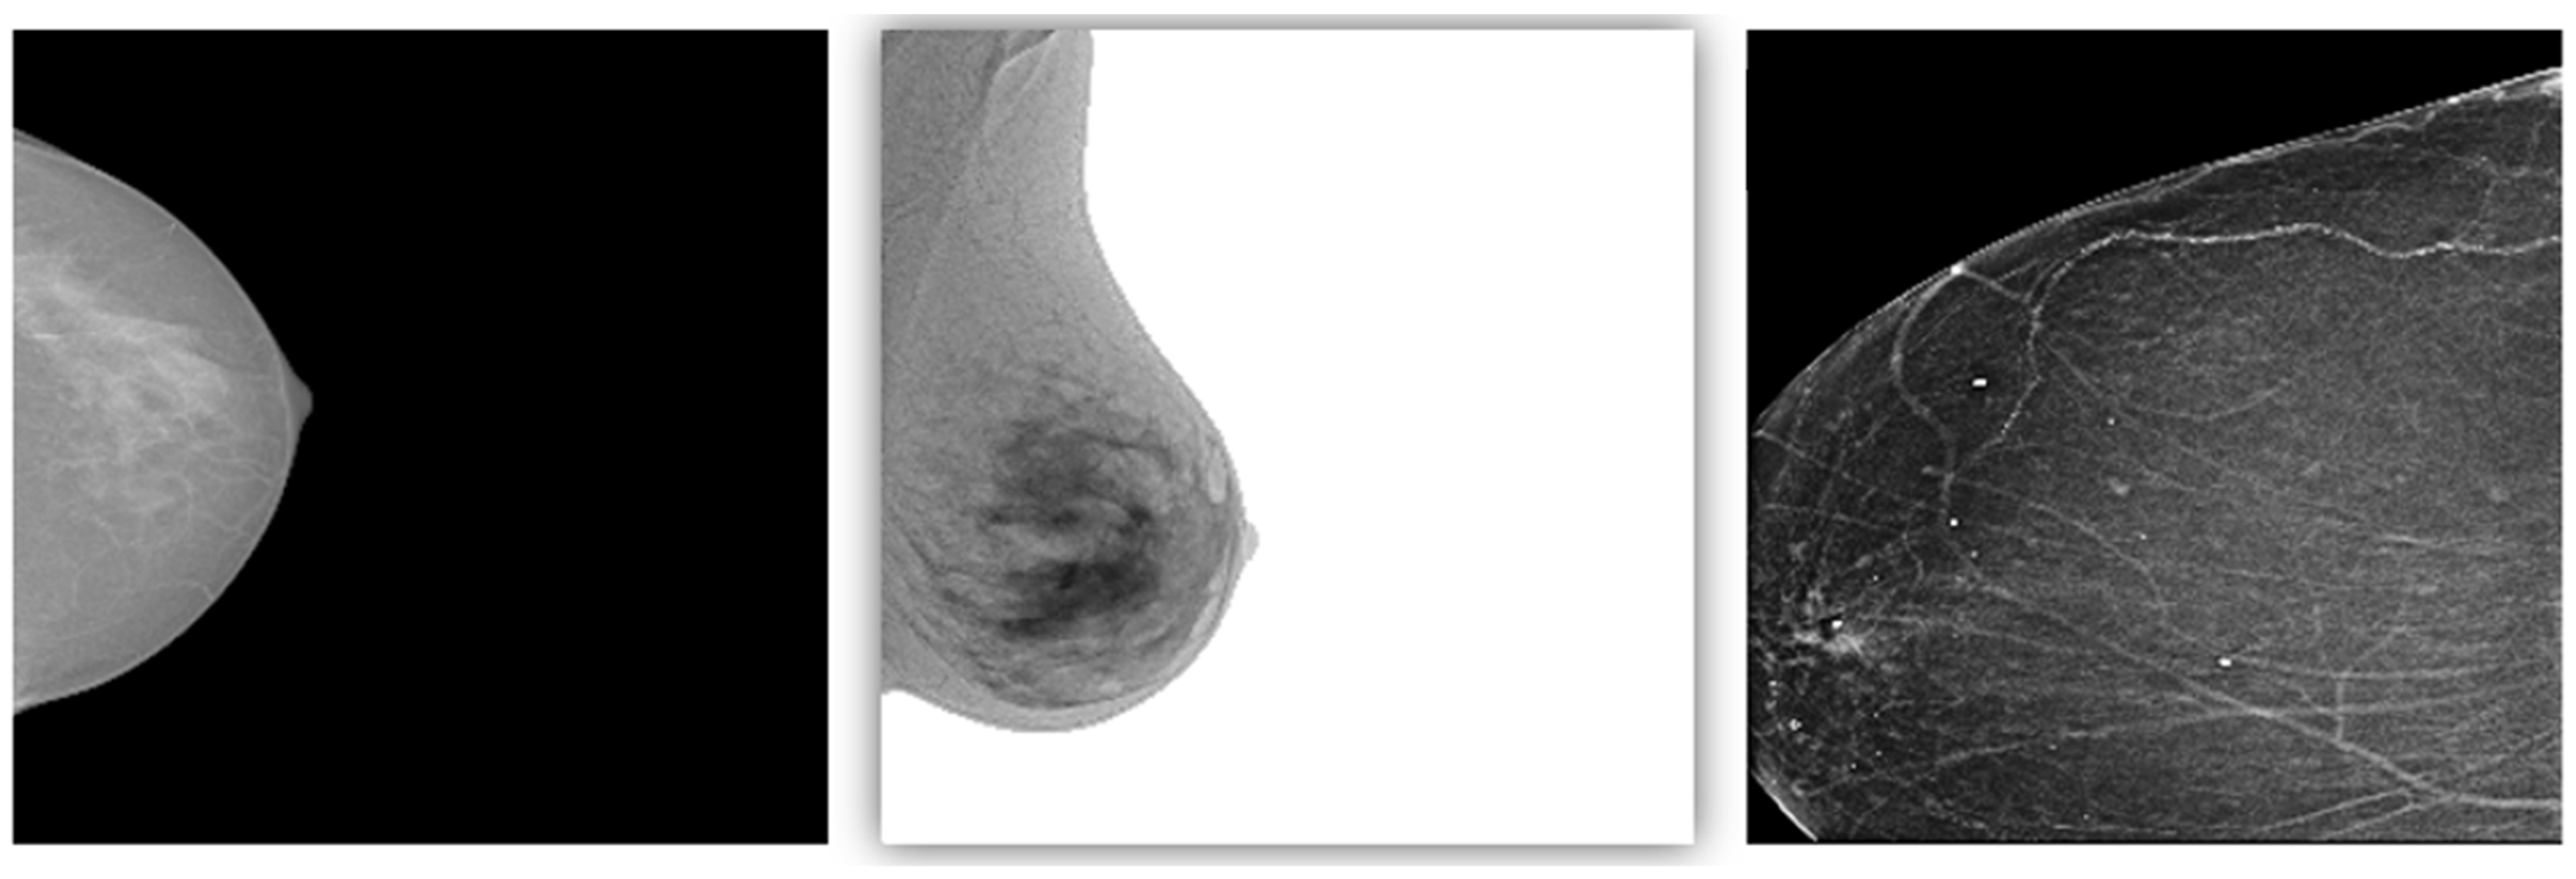

This study utilized breast images from three prominent public databases: the Radiological Society of North America (RSNA), the Polish Academy of Sciences (PAS), and Kaggle (Table 1). Table 1 provides a summary of the data sources and imaging modalities used in this study and the dataset distribution, both before and after data augmentation. The RSNA dataset contains mammography images, with 1200 benign and 1158 malignant cases, and the images were resized to 256 × 256 pixels. The Kaggle dataset includes B-mode ultrasound images, with 437 benign and 210 malignant cases, expanded using data augmentation to 1311 benign and 840 malignant cases. The image sizes in this dataset vary between 324 × 510 and 719 × 811 pixels. Similarly, the Polish Academy of Sciences dataset comprises B-mode ultrasound images, with 96 benign and 104 malignant cases originally, augmented to 288 benign and 416 malignant cases, with an image size of 256 × 256 pixels. The overall dataset after augmentation consists of 2799 benign and 2414 malignant images. The table illustrates the diversity of the data sources and modalities used in this study and highlights the role of augmentation in addressing dataset imbalances. The diversity of these datasets allowed for the development of AI models capable of performing well across different imaging modalities and patient populations. The images are categorized by modality and diagnosis: mammography (RSNA) for benign (A–C) and malignant (D–F) cases, sonography-1 (Kaggle) for benign (G–I) and malignant (J–L) cases, and sonography-2 (PAS) for benign (M–O) and malignant (P–R) cases. These images illustrate the diversity of the data sources and imaging modalities utilized for the classification tasks in this research (Figure 2).

Figure 2.

Representative examples of breast imaging modalities used in the study. The mammography (RSNA) for benign (A–C) and malignant (D–F) cases, sonography-1 (Kaggle) for benign (G–I) and malignant (J–L) cases, and sonography-2 (PAS) for benign (M–O) and malignant (P–R) cases.